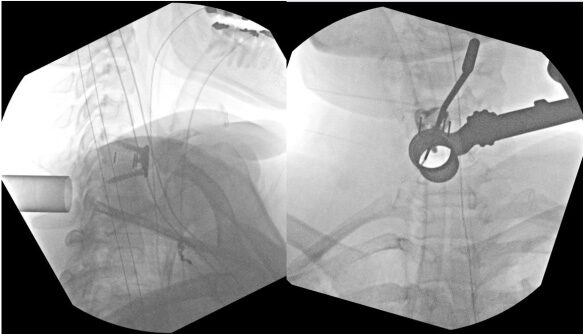

X-ray during surgery that shows the MIS tubular retractor used to access the back of the cervical spine to minimize incision size and tissue disruption.